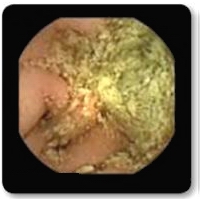

Pregătire corespunzătoare a tubului digestiv se aseamănă cu șofatul având parbrizul curat.

Pregătire necorespunzătoare a tubului digestiv poate împiedica vizualizarea totală a segmentului examinat sau poate duce la repetarea examinării după o pregătire suplimentară/corectă.